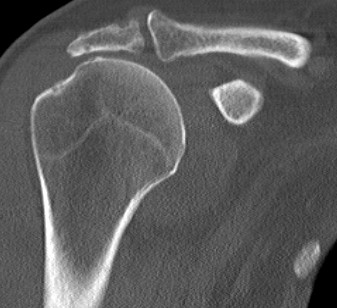

Differential diagnosis

Glenohumeral osteoarthritis

- no superior migration of humeral head

- beard osteophytes on inferior aspect of the humeral head